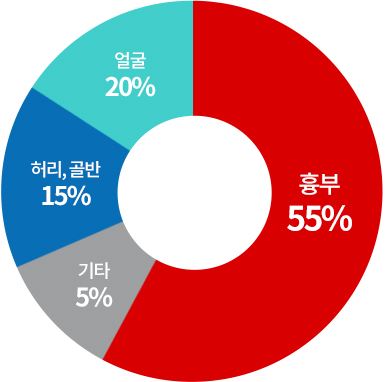

대상포진 주요 발생부위

대상포진 통증

-

수술 후 통증

14점 -

출산 분만통

17점 -

대상포진 통증

22점

대상포진 환자의 60%가 출산 때 통증보다 심한 통증을 경험합니다.